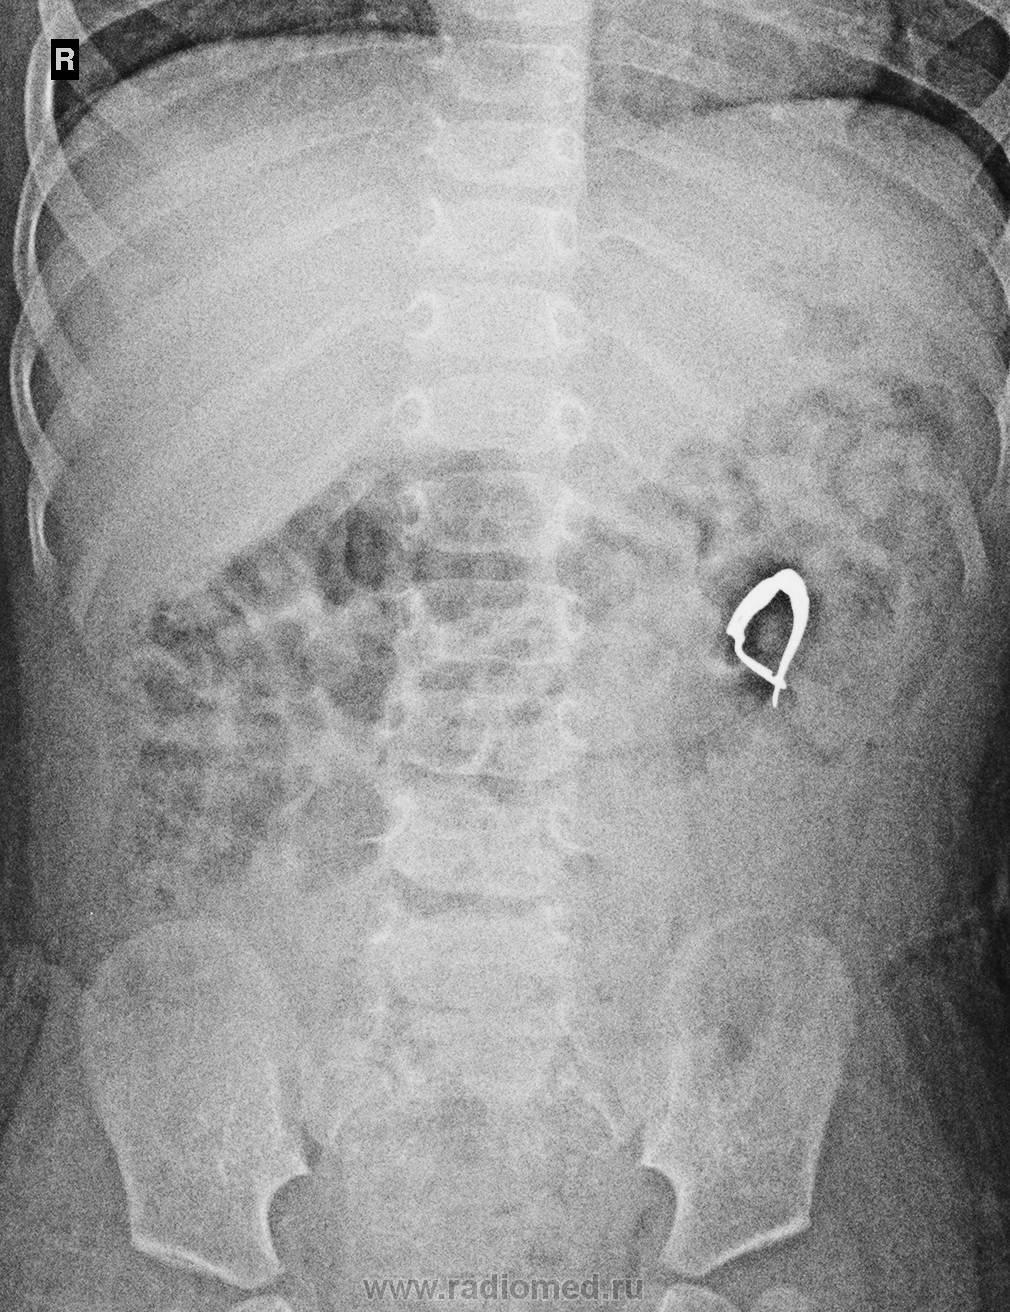

Необычные находки: инородные тела на рентгенограмме брюшной полости